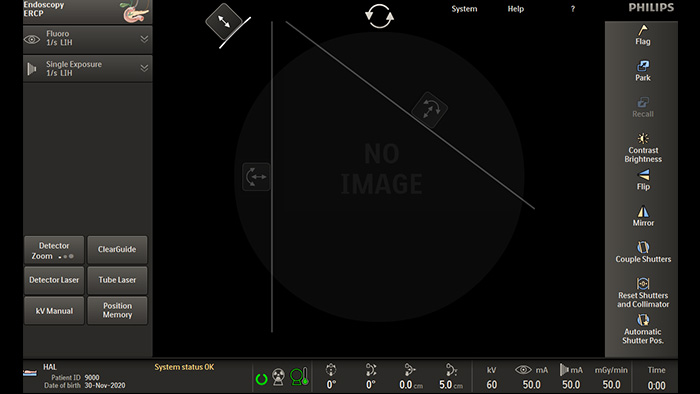

Asymmetric Collimation

Unique asymmetric shutters increase collimation flexibility and precision by allowing you to move shutters independently from each other. You can adjust shutters and image orientation while on last image hold without using radiation.